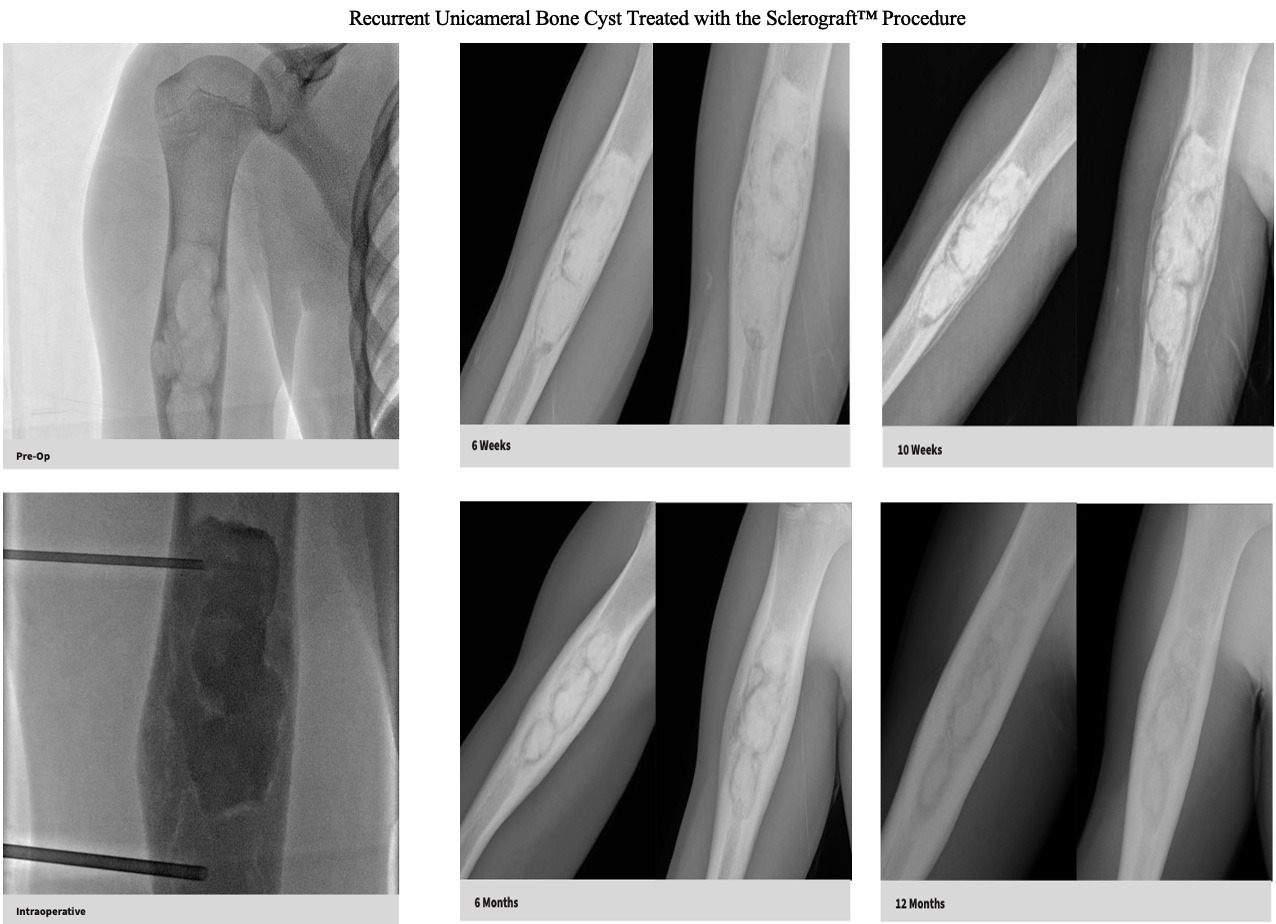

Made up of multiple small cysts and can be more locally aggressive than UBCs. They are associated with higher recurrence rates than UBCs

Utilizing needles, chemical sclerosis destroys the cyst wall and regenerative bone graft is injected via the needles to expedite bone healing.

The doctor uses imaging guidance (like X-ray or ultrasound) to guide needles into the cyst.

Chemical sclerosis using chemicals like doxycycline are washed through the cyst to kill the cyst wall lining

Regenerative bone graft is then injected through the needles and the needles are removed. The bone graft is temporary and is eventually reabsorbed by the body.

Quick recovery and bone formation seen between 6 weeks to 3 months

Low recurrence rates

Proven success in both UBCs and ABCs

Bone thickening begins to occur after approximately 6 weeks, so if you child is in a sling or uses crutches, that will be continued until the first x-ray is obtained.

Follow-up imaging is usually obtained at 6 weeks, 3 months, 6 months, 12 months and annually for at least 3 years.

The decision to return to normal physical activity is driven by how well the bone has healed based on the follow-up x-rays.

The long term follow-up with x-rays is critical because of the possibility of bone cyst recurrence. Generally, if a recurrence occurs, it tends to be noticeable by the 6 month mark

Gallery

Explore our educational resources and images